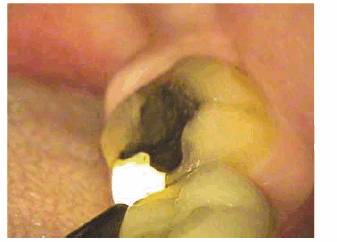

the dentinal tubules and chamber, long-term necrotic tissue (Figure 19-5), or silver precipitants from

certain root canal sealers and filling materials (Figures 19-6A 19-6B, and 19-6C). A yellow or brown (Figures 19-7A, and 19-7B) unrestored crown often represents

Figure 19-5: Discolored maxillary central incisors with necrotic pulps.

Figure 19-6A: Discoloration from silver-containing root canal cement.

Figure 19-6B: Gray color of crown from a post.

Figure 19-6C: Same radiograph as 19-6B. An unnecessary post that caused the discoloration.